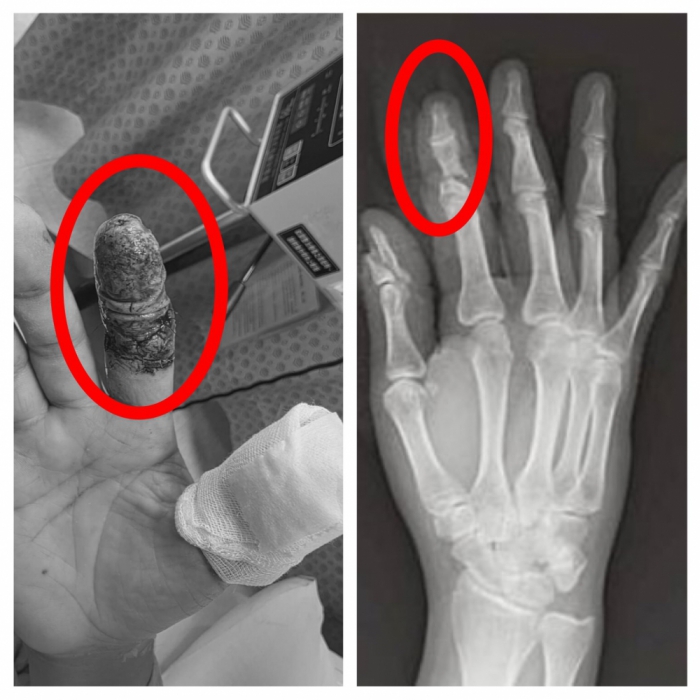

【記者林獻元台中報導】豐原一名45歲林姓男子日前操作大型無人機時發生意外,高速旋轉的螺旋槳瞬間擊中右手,食指幾乎完全斷離,僅剩少量皮膚相連,傷勢嚴重,緊急送往衛生福利部豐原醫院救治,經外科醫師陳明澤評估屬重大手指創傷,若血流未恢復恐須截指,立即進行清創與重建手術,透過顯微技術接合受損血管與組織,成功建立循環,為後續組織存活爭取關鍵時間。

豐原醫院外科醫師陳明澤指出,手指血管直徑僅約1-2毫米,顯微重接只是第一步,真正挑戰在於術後微血管血流的關鍵觀察期。陳醫師進一步表示,再接手指的血流極度脆弱,任何血栓都可能讓前功盡棄,因此團隊術後並未僅止於觀察,而是每日主動進行局部抗凝處置的特殊浸泡照護,使用的「Heparin」抗凝血藥物,採局部浸泡,輔助維持血管暢通、減少血栓形成風險,此療法屬於較細緻的術後血流管理策略,醫護人員需密集監測顏色、溫度與出血反應,是術後照護能力的重要延伸。